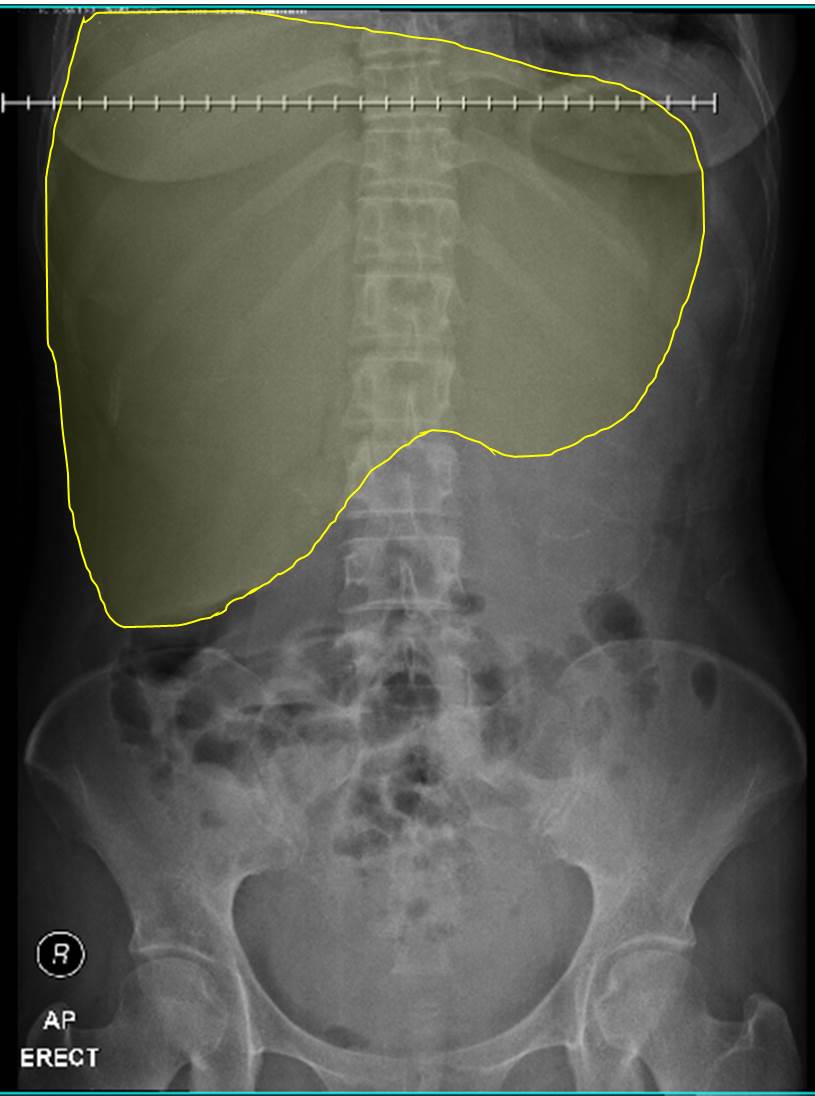

from www.researchgate.net

an elevated hemidiaphragm may result from direct and indirect causes which include: elevated hemidiaphragm is a condition where one portion of the diaphragm is higher than the other. Up to 90% of unilateral diaphragmatic palsy can be diagnosed. explore the causes, symptoms, diagnosis, and management of an elevated hemidiaphragm, a condition characterized. unilateral diaphragm paralysis is often first suspected after the finding of an abnormally elevated hemidiaphragm on a. elevated hemidiaphragm is a condition where one portion of the diaphragm is higher than the other. on the left side, a big stomach filled with food or gas can cause the diaphragm to appear elevated. elevated hemidiaphragm is a condition where one portion of the diaphragm is higher than the other. if the left side is paralyzed, both hemidiaphragms will appear at the same level.

Chest Xray before diaphragm plication. The left diaphragm was elevated